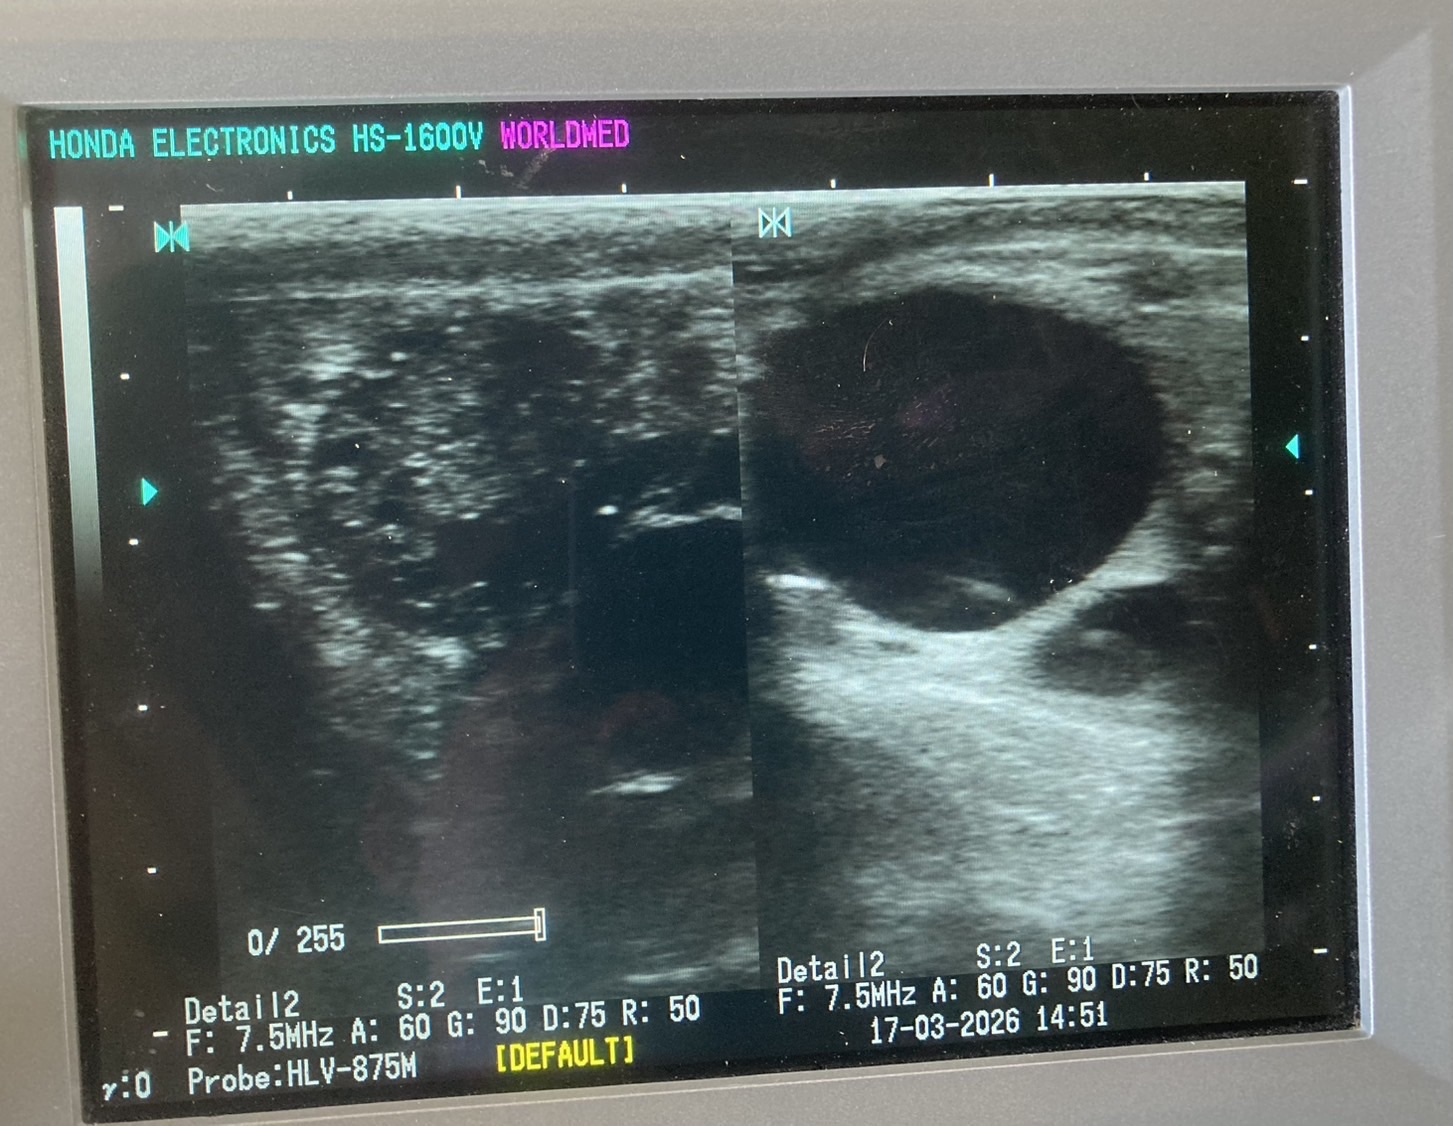

ตรวจท้องโคนม จำนวน 3 ตัว (พบโคท้อง 1 ตัว)

ตรวจระบบสืบพันธุ์ พร้อมแก้ไขปัญหา จำนวน 2 ตัว